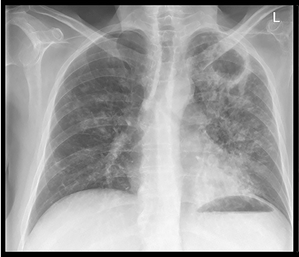

73yo male with no PMH comes to clinic with complaint of fever and SOB/cough. He has intermittent lower right chest pain, and poor appetite for 3 days, but otherwise is okay. Denies N/V/D or abd pain. He is not confused. On exam he is mildly tachycardic, tachypneic, SpO2 is 91%, has no WOB, but does have some RLL consolidation on egophany testing. CXR ordered in clinic.

What is his CURB65? What is treatment dose?

Community Acquired Pneumonia